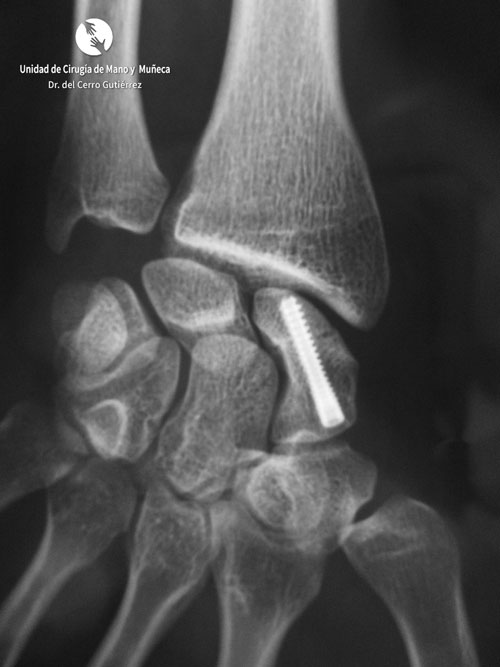

Fractura del Escafoides. Fractura del Polo Proximal

Fractura del Polo Proximal

Fractura del Escafoides Pseudoartrosis escafoides injerto con tornillo

Pseudoartrosis escafoides injerto con tornillo